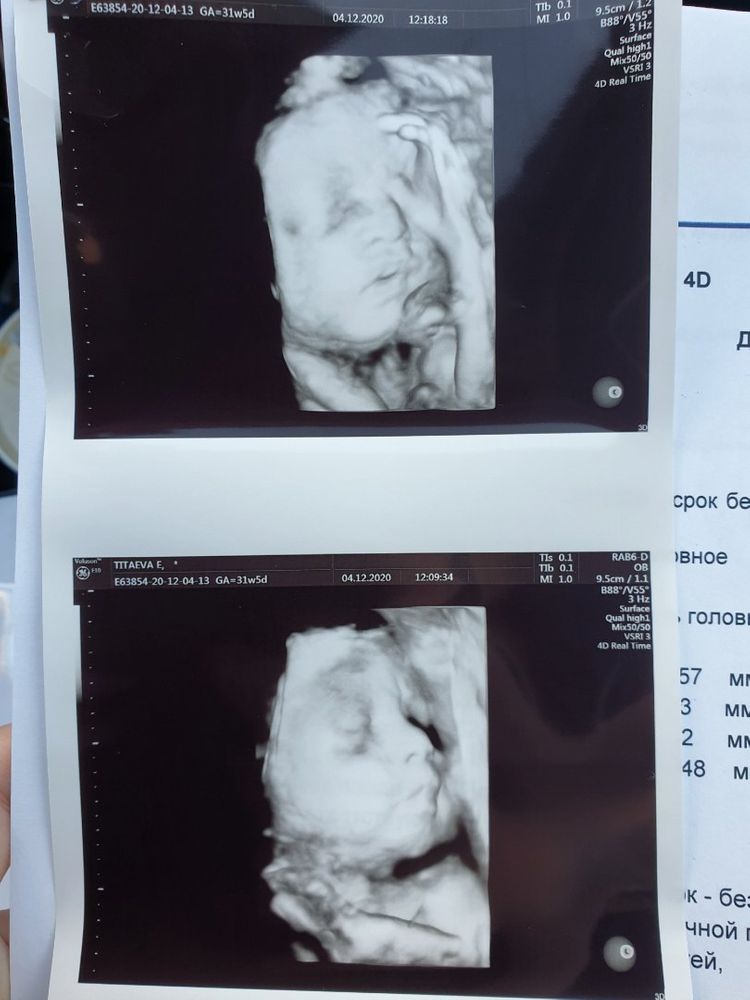

Изображение Наше УЗИ в 30 недель, глаза как у инопланетянина 👽😁

Мне по 3д фотке а 30 нед, тоже носик показался 'расплющенным', я даже пост создавала, что по фото носик у нас будто как у особенного малыша, мне здесь девчата быстро мозги на место вправили) Малыш слава Богу родился здоровым и красивым. 😊🙏 По поводу глазок, у нас до 1.5 месяца он был на азиата похож, раскосые были глазки, сейчас большеглазый лупоглазик. (это ничего плохо в адрес национальности, я просто к тому, что детки меняются) Не переживайте, не накручивайте себя, все отлично у Вашего малыша.

Ну это же у Вас фото.! Даже если взрослого сфотографировать, сами знаете, что могут быть фото не удачные🥴даже у новорождённых, первый месяц глазки плавают